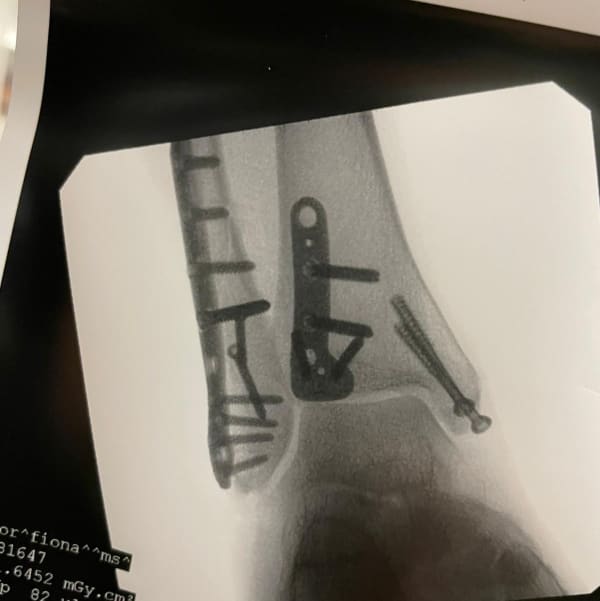

Fiona Taylor On the evening of the 7th April I fell bouldering. Originally we believed this was just a dislocation that would be fixed quickly as I was not in much pain but the paramedics made it obvious it was likely much worse getting me quickly on morphine and strapping me up. The X-rays in the emergency department confirmed their suspicions, I had broken my ankle and not to do things half arsed I had in fact dislocated my ankle and fractured all three bones - a trimalleolar or trifecta as I like to call it. In the ED they attempted to manoeuvre my foot back into place as best they could before the first plastering. Apparently I would be sedated and therefore be semi awake, feel no pain and likely not remember any of it. At this point I still wasn’t experiencing pain, more like an ache unless it was bumped or moved. I felt nothing as they performed this resetting but I was fully conscious and chatting to them throughout the process. Having only had 15 mg of morphine when the paramedics first arrived and a few sucks on a green whistle they were all rather surprised my pain hadn’t increased once the shock and adrenaline wore off, perhaps Us London folk are just raised tougher! A lack of beds on orthopaedics meant I slept the first hour that night in the plaster room and then was moved to a a neuroscience ward about 4am and was nil by mouth expecting an operation the following day.

9 Apr 202144-48 Cowper Street

Fiona Taylor After waiting nil by mouth for surgery again the surgeon finally came to meet me and take a look and talk through the surgery. It’s not gonna be a simple surgery, screws plates and likely 3 incisions, one on each side and one up the back from heel to calf, they’d need to see the state of the tendons and ligament once they open it up. A plate may also be needed at the front which would likely mean a second op later to remove it. Unfortunately on removing the bandages and opening the front of the cast he advised I’m still too swollen and will be sent home until the swelling has gone down enough to operate. I’m to return on Monday ( 3 days later) to see if it’s reduced enough to schedule the surgery. Leave on crutches for a weekend of rest at home

Fiona Taylor Day of surgery (finally!) After failed surgeries due to swelling and emergencies trumping me I finally succumbed to going fully private. I was initially going private in public to support the quite significant gap for both surgeon and anaesthetist however my surgeon offered a reduced rate as I’d been bumped twice. More calm via the private hospital, you’re admitted quickly at your given time, get changed and the wait in the lounge until surgery. For me this was a couple of hours from arrival. The aneasthetists staff talked me through what was to happen, I had a quick chat with my surgeon and the actual anaesthetist but don’t remember anything after that not even a “count to...”! I woke up in recovery like a bit of a space cadet. Apparently the surgeons registrar had been to see me but I had no recollection of that. I was in more pain than I had previously been so the nurse kindly worked with me to find the right threshold on painkiller before I could be moved to the ward and see my boyfriend. I was in recovery for a good couple of hours and without use of my phone, apparently because you won’t remember what to say or hear anyway at first which was definitely true of my conversation with the registrar. Fortunately my nurse repeated the all clear back to me later when I complained they hadn’t bin!